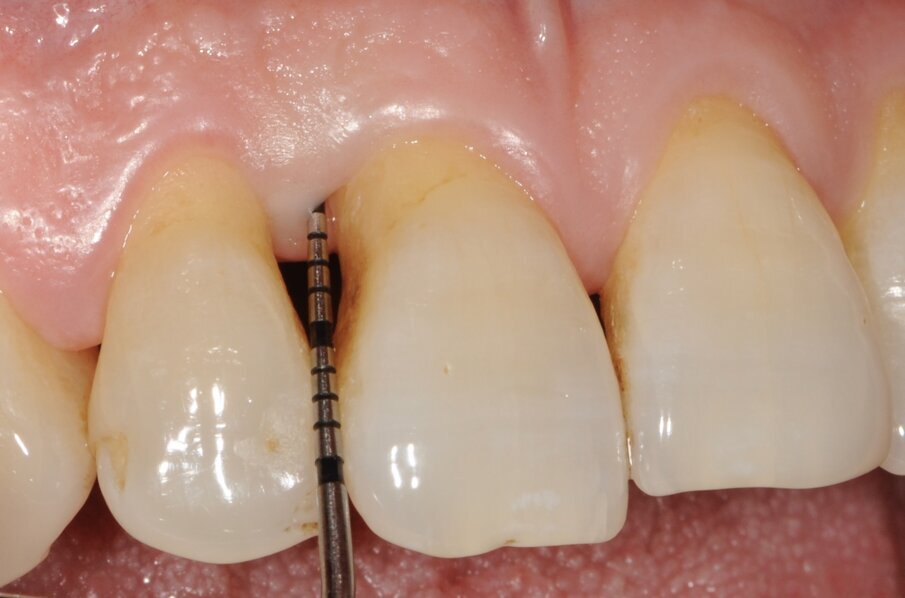

Un paziente di 56 anni non fumatore viene riferito alla nostra osservazione per il trattamento della parodontite. Dopo aver effettuato la diagnosi (parodontite generalizzata Stadio III, Grado C) il paziente è sottoposto a due sedute di scaling sopra gengivale (step 1) e successivamente a 4 sedute di debridement sotto gengivale effettuato con strumenti ultrasonici e manuali (step 2). Al momento della rivalutazione si registra un miglioramento degli indici di placca e di sanguinamento (FMPS e FMBS ≤ 20%) e una riduzione di tutte le tasche parodontali (PD<4 mm) in ciascun sestante a eccezione del secondo sestante. In questa regione si registra una tasca residua con PD = 6 mm a carico dell’elemento 1.1, associata a un riassorbimento osseo radiografico prevalentemente orizzontale (Figg. 1, 2). Considerando il miglioramento di tutti i parametri e degli indici parodontali e la presenza di una tasca con PD = 6 mm a carico di un solo elemento dentario si decide di ritrattare l’elemento 1.1 con terapia non chirurgica (step 3). La nuova ristrumentazione è stata effettuata seguendo il protocollo Clean&Seal che prevede l’associazione di ipoclorito di sodio stabilizzato con amminoacidi e acido ialuronico reticolato ad alto peso molecolare in combinazione con il debridement sotto gengivale. Dopo anestesia locale, è stato applicato all’interno della tasca l’ipoclorito di sodio stabilizzato con amminoacidi e lasciato agire per circa 60 secondi (Fig. 3). Successivamente è stata effettuata la strumentazione sotto gengivale mediante l’utilizzo di strumenti ultrasonici e manuali (Figg. 4, 5). Alla fine della procedura di strumentazione, nella tasca è stata effettuata un’irrigazione con soluzione salina sterile e la procedura di applicazione di ipoclorito di sodio e di strumentazione meccanica è stata ripetuta per 4 volte. Un fattore critico per garantire un risultato migliore è di evitare di instillare qualsiasi soluzione a base di clorexidina nella tasca, in quanto inibisce l’adesione cellulare. Alla fine del trattamento meccanico è stato inserito l’acido ialuronico reticolato ad alto peso molecolare all’interno della tasca per stabilizzare il coagulo e accelerare la guarigione (Fig. 6). Il controllo clinico è stato effettuato dopo 6 settimane dal trattamento con completa chiusura della tasca (Fig. 7).